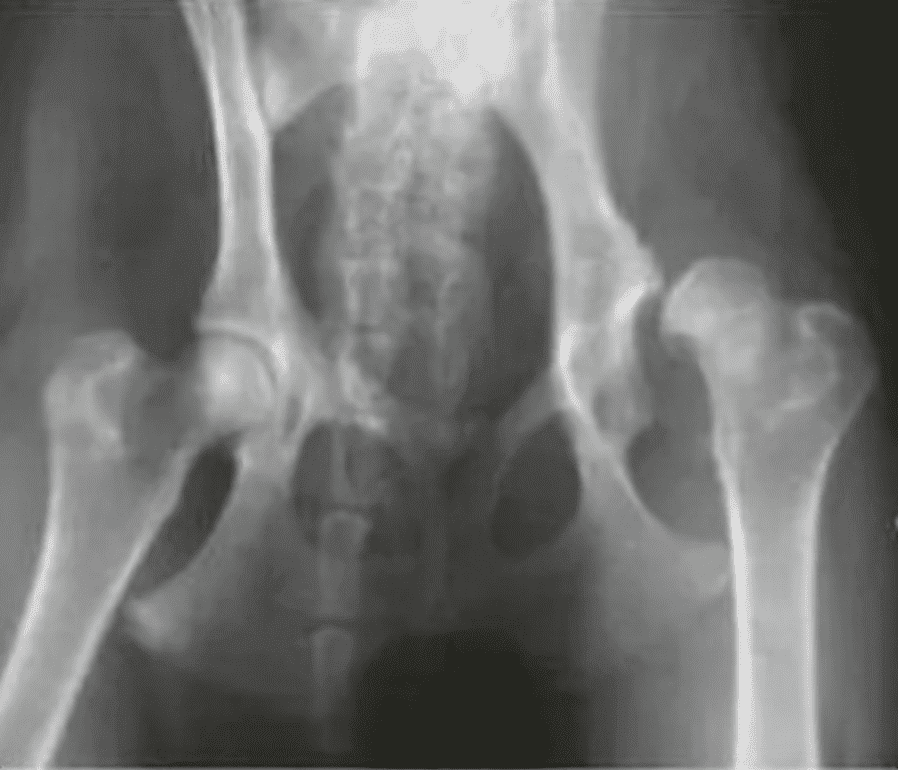

Aby w pełni zrozumieć znaczenie wynalazku, warto wyjaśnić, czym jest dysplazja. To schorzenie może wystąpić u psów w każdym wieku, ale jeśli zostanie zdiagnozowane przed ukończeniem 6. miesiąca życia, istnieje szansa na wyleczenie. W przypadku dysplazji proces formowania stawu zostaje zakłócony, co prowadzi do uszkodzenia panewki stawu, w której osadzona jest ruchoma część kości – głowa kości udowej. Weterynarze podkreślają, że jest to choroba dziedziczna, dlatego właściciele powinni bacznie obserwować swoje zwierzęta, aby w porę zauważyć objawy.

Autorzy wynalazku dogłębnie analizowali ten problem i doszli do wniosku, że dysplazję można skutecznie leczyć. Według Uniwersytetu Rolniczego w Krakowie epidemiologia choroby u psów sięga nawet 65%, co jest bardzo niepokojącym wskaźnikiem. Jednym ze sposobów walki z dysplazją jest potrójna lub podwójna osteotomia miednicy, która polega na osłonięciu głowy kości udowej i zwiększeniu powierzchni podparcia w obrębie chrząstki, co ogranicza rozwój zwyrodnienia stawu biodrowego. Taka operacja nie eliminuje jednak całkowicie choroby, wymaga stałego monitorowania i stosowania leczenia podtrzymującego.